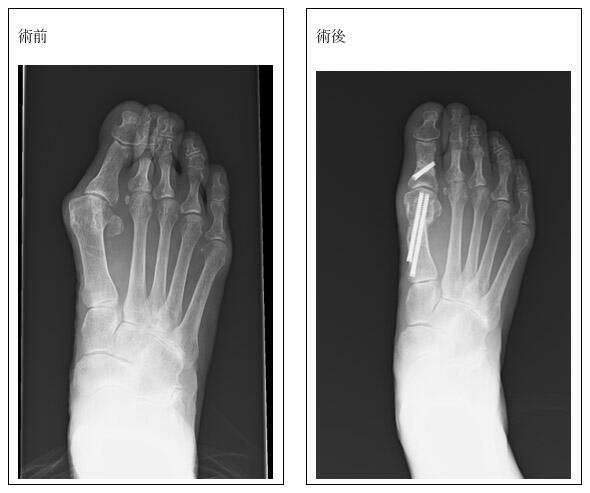

●スポーツ・足班

足部・足関節(足首より先)の傷害全般および膝関節のスポーツ障害を対象に、低侵襲治療をモットーとして診療を行っています。

研究面では、アスリートにおけるスポーツ傷害の実態調査や予防に関する研究、高齢者の介護予防・健康寿命延伸を目的とした疫学研究・介入研究を進めています。

また、腱修復促進をテーマとした基礎研究にも取り組んでいます。